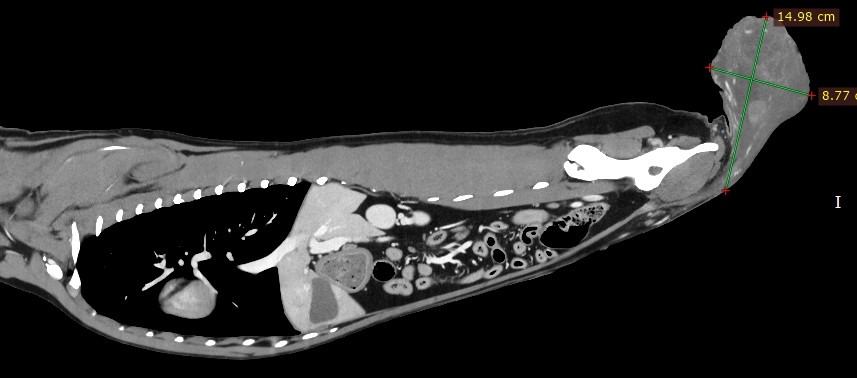

10歳、19kg

その前にCT検査で転移の確認

どこかお解りですよね

診断:陰嚢腫瘍、前立腺肥大症

this case is a scrotal tumor.

so big and hard

it is painful.